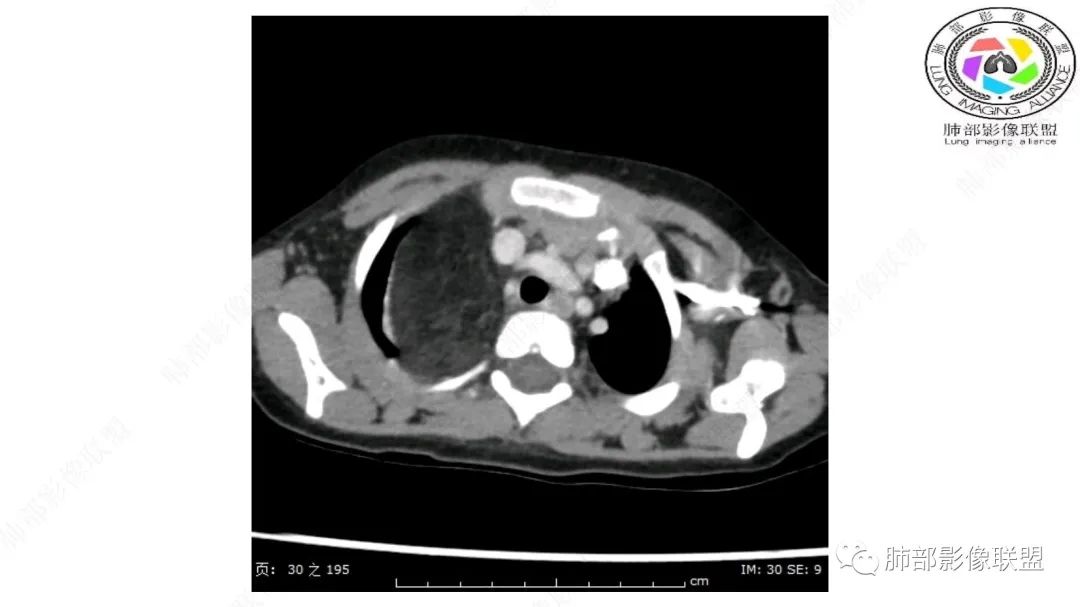

右上纵隔混杂密度肿块,边缘光整,与纵隔分界清,其内多发脂肪密度,增强无明显强化,其内血管穿行,考虑纵隔脂肪母细胞瘤,鉴别畸胎瘤,脂肪肉瘤。

患儿3岁 咳嗽检查发现纵隔占位。右肺上叶受压表现,占位以脂肪组织密度为主,似见分隔,首先考虑为脂肪母细胞瘤,鉴别脂肪瘤,畸胎瘤。

幼儿,右上纵隔团块状脂肪密度影,边缘清晰,内可见血管及支气管穿行,考虑脂肪瘤,鉴别畸胎瘤。

幼儿,右上纵膈团块,脂肪密度,内见分隔,增强病灶内见血管穿行,结合患者年龄,考虑脂肪母细胞瘤,鉴别脂肪瘤。

纵隔畸胎瘤,右前上纵隔团状脂肪密度?粘液样密度为主病变,病灶软边缘有分叶,内可见分隔,增强后血管穿行。3岁。考虑纵隔脂肪母细胞瘤,鉴别畸胎瘤。

病灶属于交界区,主体位于肺内,占位效应明显,前方突入胸壁,胸腺受压变形,胸膜显示欠清楚;病灶包绕上叶肺动脉;似乎有体动脉供血。符合肺内的点:包绕上叶肺动脉分支;符合纵隔的点:前方似乎突入胸壁,与胸腺关系比较密切,但是与上腔静脉的关系提示病灶不支持纵隔来源,前纵隔的常规会将上腔静脉受压后移、外移,这是不符合的。